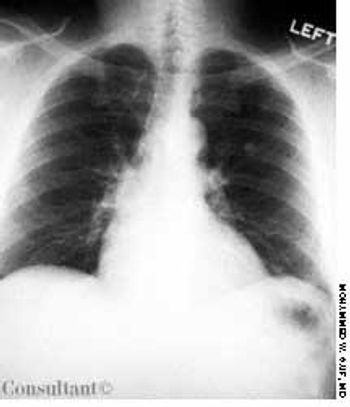

Over the past 6 months, a 72-year-old man was troubled by a persistent cough; he also had lost 9 kg (20 lb). He had no fever or chills, but he noticed mild streaking of blood in his sputum during the past month. He had been a cigarette smoker for 50 years.

A 60-year-old woman with a 3-month history of cough, chest pain, and shortness of breath was brought to the emergency department. The patient denied any history of fever, chills, or rigors; she complained of mild hemoptysis for 1 week and a 9-kg (20-lb) weight loss during the last few months. The patient had smoked cigarettes for 40 years.

During the past few months, a 50-year-old woman had experienced cough, dyspnea, mild hemoptysis, and a 30-lb weight loss. She had no fever, chills, or rigors. The patient had smoked cigarettes for 30 years.

A 67-year-old man with a 5-month history of cough, shortness of breath, and pain in the left anterior chest wall sought medical evaluation. The patient denied fever, chills, and hemoptysis. He reported a recent weight loss of 25 lb. The patient had smoked cigarettes for 37 years.

For the past 3 months, a 72-year-old man has had progressivelyworsening dyspnea on exertion and constantvague discomfort in the left chest that appears to have apleuritic component. He denies paroxysmal nocturnaldyspnea and has no history of chest trauma. However, hehas a chronic cough that sometimes produces purulentsputum-although it is not associated with hemoptysis.His feet swell occasionally, and he has mild anorexia andhas lost 20 lb in 6 months.